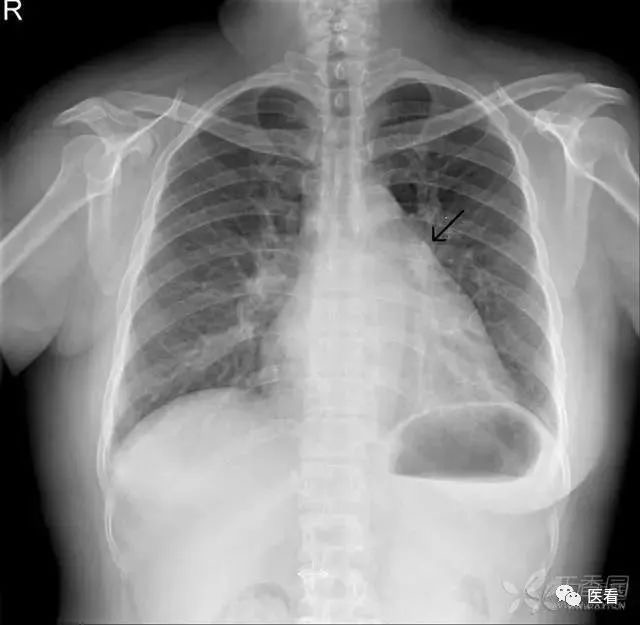

又称二尖瓣型心。肺动脉段凸出及心尖上翘,主动脉结节缩小或正常,状如梨形。多见于右心负荷或以其为主的心腔变化。常见疾病有二尖瓣病变、房间隔缺损、肺动脉瓣狭窄、肺动脉高压和肺心病等。

梨形心,左房、右室扩大,肺动脉段突出(箭头示),肺纹理增粗。